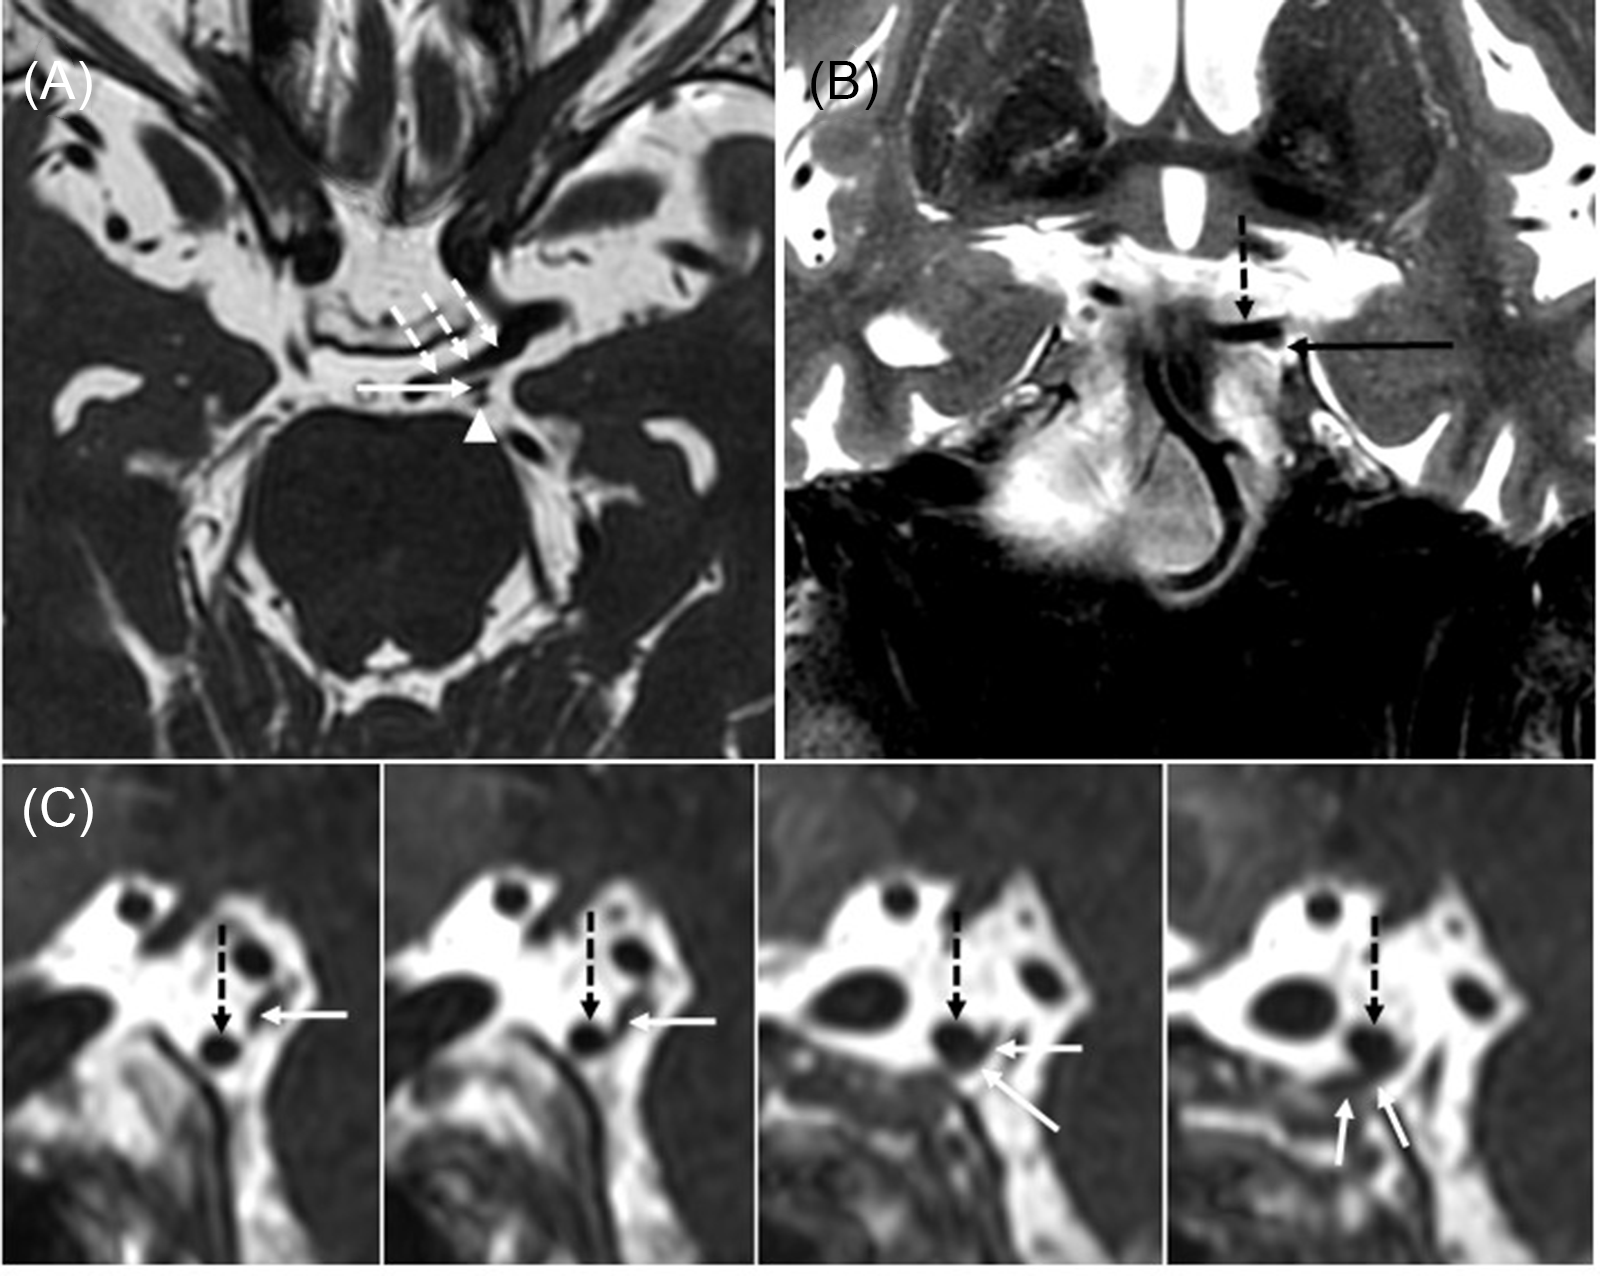

A diagnosis of partial pupil-sparing left TNP was suspected and an MRI and MR angiography of the brain and orbits with contrast was performed. It revealed bilateral, left more greater than right, dolichoectatic PCommA with the left PCommA abutting and displacing the third nerve (Figure 1). There was no aneurysmal dilatation of the affected vessel wall.

Figure 1: Large left posterior communicating (PComm) artery displacing the left oculomotor nerve. (A) Axial 3D FIESTA sequence shows a large left PComm artery (dashed arrows), the left oculomotor nerve (arrow), and the left superior cerebellar artery (arrowhead). (B) Coronal T2-weighted image shows the left oculomotor nerve (arrow) coursing along the undersurface of the left PComm artery (dotted arrow). (C) Series of sagittal reformats from the 3D FIESTA sequence shows the left PComm artery (dotted arrows) indenting the left oculomotor nerve (arrows).